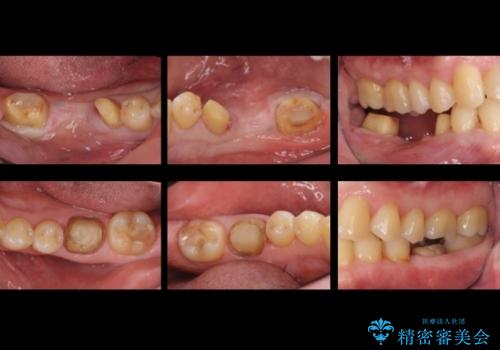

- 受け口を主訴に来院。

他院での矯正相談は、5年以上かかると言われ、やんわりお断りされたとのことでした。

ずっと矯正はしたかったがあきらめていて、50代で退職を機に新しいことを初めて、歯並びも諦めずに治したいとのことでした。顎の手術は避け、歯の移動だけでの治療をご希望されていました。

右上の八重歯は、右上の奥歯を矯正用ミニスクリューを用いて遠心移動を行い解消しました。

下の前歯はIPR(エナメル質を薄く削り歯を小さくする処置)を行なっています。